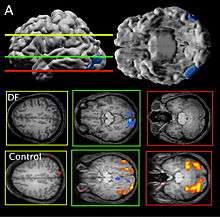

Patient DF’s brain damage resulted from hypoxia due to carbon monoxide poisoning.[2] The lateral occipital cortex in her brain is severely damaged and shows no activation presented with line drawings of common objects where healthy people usually do. There is also some shrinkage in the intraparietal sulcus, often implicated in the dorsal stream for visuomotor control. The fusiform face area is intact. This would suggest the problem in DF’s perception is disconnectivity between higher and lower order functioning.[2]

Recent MRIs have shown many enlarged sulci, like the intraparietal sulcus, parieto-occipital sulcus, and left calcarine sulcus, indicating atrophy.[2] Her visual field remains intact up to 30 degrees.[1]

DF does not benefit from haptic feedback—allowing her to pick up an object does not let her better estimate its width next time.[3] DF also does not use visual information about her grasp: when she can only see her grip in a distorted mirror, her performance does not change.[2] Consistent with all of this, brain imaging has shown no response to line drawings in her ventral stream. Furthermore, according to fMRI studies,the intraparietal sulcus showed preference for grasping motions over reaching motions—actually grabbing an object, in both DF and control patients, activates the intraparietal sulcus more than reaching.[2]